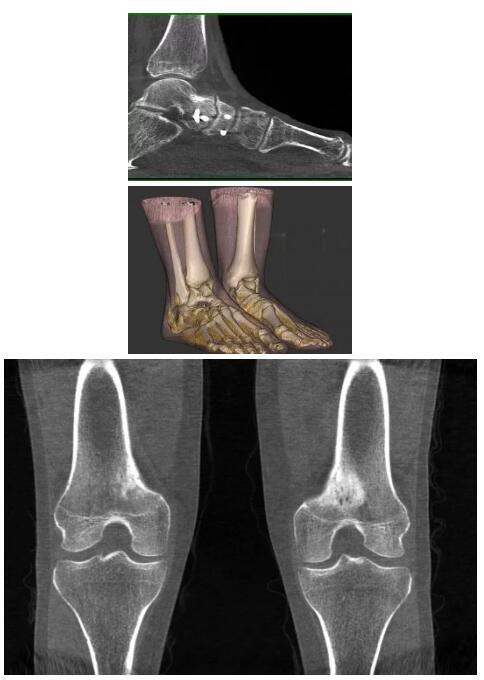

比如上面這款專(zhuān)用于足部和踝部掃查的CT成像系統,患者在進(jìn)行CT掃查時(shí)只需要站在上面即可,雙腳站或者單腳站都可以,當然,如果患者不是那么方便站著(zhù)做完CT掃查,也可坐在上面。

這款CT掃查系統自帶屏蔽裝置,它的體積非常小,僅需要極小的空間即可,并不像常規CT那樣需要一間單獨的檢查室。此外,這種CT掃查的速度非???,僅需30秒左右可以完成檢查,輻射劑量相對常規的CT要少許多,尤其適合醫院的骨科使用。

而患者站著(zhù)做足部或者踝部做CT檢查還有個(gè)好處是,可以檢查患者在負重的情況下,骨關(guān)節的真實(shí)情況,而躺著(zhù)做CT掃查時(shí)未必能看出來(lái)。負重CT掃查特別是對于受傷的運動(dòng)員或者舞蹈員來(lái)說(shuō)意義更大,能夠更準確地評估傷情,幫助他們盡早復原。

以下是這些“特立獨行”的CT所拍出來(lái)的圖像: